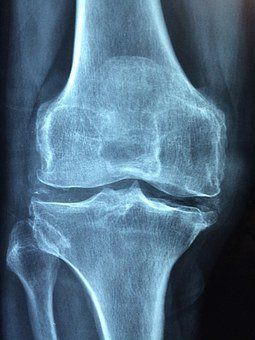

Es ist relativ unbekannt und zum Glück einigermaßen selten, aber auch Kinder können an Rheuma erkranken. Die häufigste rheumatische Krankheit bei Kindern ist das sogenannte Juvenile Idiopathische Arthritis - JIA, umgangssprachlich auch Gelenkrheuma genannt. Juvenil bedeutet, dass die Erkrankung spätestens innerhalb des 16. Lebensjahres beginnt, idiopathisch bedeutet, dass die Ursache unbekannt ist und Arthritis bedeutet, dass eine Gelenkentzündung vorliegt. An dieser Erkrankung erkranken jedes Jahr erneut rund 1.200 Kinder und Jugendliche.

JIA wird als Überbegriff für folgende Erkrankungsformen verwendet: Oligoarthritis, systematische Arthritis, Polyarthritis, Psoriasis-Arthritis und Arthritis mit Enthesitisneigung.